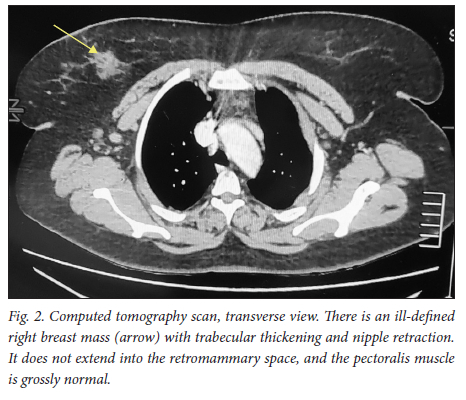

A 39-year-old obese woman had had a lump in the right breast for 18 months. She had gone to her local hospital when she noticed the lesion. A core biopsy was done and she was referred to the breast oncology clinic at Mankweng Hospital in Polokwane, Limpopo Province, South Africa, for further assessment and management. She had previously been healthy, with no known comorbidities and no family history of malignancy. On enquiry about her gynaecological history, she stated that her menarche had been at age 12, and she was still having normal periods and on contraception. She had a 15-year-old child, born when she was 24. After the birth of this child she had two more pregnancies, both resulting in unexplained stillbirths at term. She had no history of pregnancy-induced hypertension or any medical conditions diagnosed during pregnancy. After her discovery of the breast lump she was diagnosed with young-onset hypertension. There were no associated weight changes, and she was HIV negative. On examination she had a scar on the right upper quadrant, no palpable axillary lymph nodes, an elevated blood pressure (150/93 mmHg, pulse rate 88 bpm) and a high body mass index (37.7 kg/m2). The rest of the vital signs and the findings on systemic examination were unremarkable. On examination of the breast, the tumour was clinically staged as T3N0M0, making it stage IIB. Histological evaluation showed nests of cells infiltrating extensively throughout the tissue. The cells were hormone receptor (oestrogen and progesterone) positive, the HER2 score was 3+ and the Ki-67 proliferation index was 50 - 60%. Synaptophysin (SYP) and chromogranin (CGA) cytoplasmic staining was positive within the tumour cells, features in keeping with grade 3 invasive carcinoma showing neuroendocrine differentiation. A mammogram (Fig. 1) revealed poorly marginated density with a speculated mass noted on the upper inner quadrant at 1 o'clock on the middle portion of the right breast. The mass expended anteriorly to the retro-areolar space causing minimal traction of the peri-areolar skin and nipple. There were associated architectural distortions and trabecular thickening. The retromammary space was grossly normal bilaterally. There was no thickening of overlying skin, and no dilated ducts bilaterally. Regional benign calcifications were noted in the left breast. No axillary lymph nodes were visualised bilaterally. For further evaluation, a computed tomography (CT) scan (Figs 2, 3 and 4) was done and revealed multiple enlarged lymph nodes in the right axillary region. The right breast was ill defined with trabecular thickening and nipple retraction. The breast mass did not extend into the retromammary space, and the pectoralis muscle was grossly normal. Hypodense areas were noted in the thoracic and lumbar vertebrae, with involvement of the posterior elements. The right scapular blade and spine also had multiple hypodense areas. The lung parenchyma, the visualised liver, the stomach and the rest of the visualised bowel and the kidneys were grossly normal. With this evidence, the patient was diagnosed as having primary NEBC, with features suggestive of metastasis to the bones. A bone scan revealed widespread metastases in the skull and throughout the spine, pelvic bone, proximal femur and sternum. In view of this finding, the patient was re-assessed as having clinical stage IV disease. The management approach changed to focus on palliative care. There was no surgical intervention, and the patient was referred to the medical oncology clinic for further management, to come back if the need for surgical palliation arose.

Primary NEBCs are rare and the diagnosis therefore depends on excluding metastasis from other sites, because the two entities require different management approaches.[9] Diagnostic tools include the use of tumour markers such as CGA and SYP immune reactivity, which is significantly associated with a neuroendocrine neoplasm.[1,10] Importantly, elevated CGA levels are also associated with hypertension, obesity and heart failure,[11] among other conditions. On breast imaging with mammography and/or ultrasound, secondary NEBCs are oval in shape, with circumscribed or microlobulated margins.[12] Triple assessment is mandatory; however, histopathological assessment and immunohistochemistry staining are the mainstay of diagnosis. [1,13,14] Clinically, the presentation of NEBCs cannot be distinguished from other types of breast cancer. It has also been postulated that, unlike other breast cancers, NEBCs can present with clinical features related to hormonal secretion because of ectopic production of adrenocorticotrophic hormone, norepinephrine or calcitonin.[15] Our patient was obese and hypertensive, with SYP- and CGA-positive cytoplasmic staining within the tumour cells. More knowledge and research on the possible association between the tumour markers and clinical syndromes could play a vital role in patient management, so further evidence on this association is of crucial importance. So far, there are no available research data specifying radiological pathognomic features in the diagnosis of NEBCs. As in our patient, mammographic and CT scan findings are similar to those in other histologically different types of breast cancer, and imaging therefore cannot be used alone. It is vital to distinguish between primary NEBCs and metastatic neuroendocrine tumours from another site, because treatment of the two is different.[15] The CT scan findings in our case suggested that the patient had advanced breast cancer with metastasis to the thoracic vertebrae, right scapular blade and spine. With no specific management strategies for advanced neuroendocrine breast malignancies, the management principles are currently the same as for other types of breast cancers. A multimodality therapeutic strategy includes chemotherapy, endocrine therapy, peptide receptor radionuclide therapy, radiation therapy or surgery, or combinations of the above. It is hoped that better knowledge of the biology of these tumours will provide new therapeutic targets for personalised treatment in the near future.